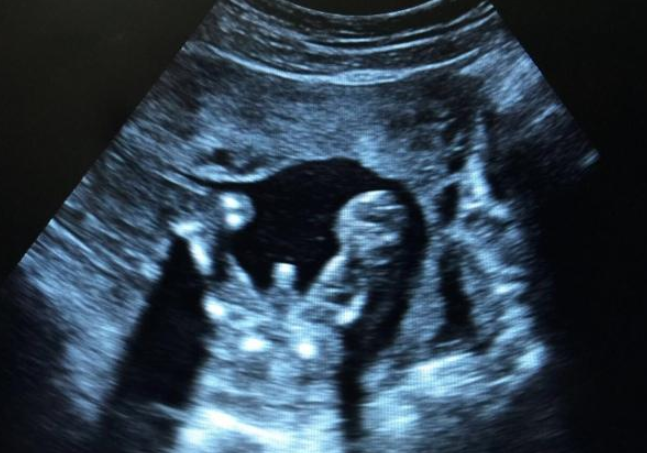

4周:胎兒只有0.2厘米。受精卵剛完成著床,羊膜腔才形成,體積很小。超聲還看不清妊娠跡象。

5周:胎兒長到0.4厘米,進入了胚胎期,羊膜腔擴大,原始心血管出現,可有搏動。B超可看見小胎囊,胎囊約占宮腔不到1/4,或可見胎芽。

6周:胎兒長到0.85厘米,胎兒頭部、腦泡、額面器官、呼吸、消化、神經等器官分化,B超胎囊清晰可見,并見胎芽及胎心跳。

7周:胎兒長到1.33厘米,胚胎已具有人雛形,體節已全部分化,四肢分出,各系統進一步發育。B超清楚看到胎芽及胎心跳,胎囊約占宮腔的l/3。

8周:胎兒長到1.66厘米,胎形已定,可分出胎頭、體及四肢,胎頭大于軀干。B超可見胎囊約占官腔1/2,胎兒形態及胎動清楚可見,并可看見卵黃囊。

9周:胎兒長到2.15厘米,胎兒頭大于胎體,各部表現更清晰,頭顱開始鈣化、胎盤開始發育。B超可見胎囊幾乎占滿宮腔,胎兒輪廓更清晰,胎盤開始出現。

10周:胎兒長到2.83厘米,胎兒各器官均已形成,胎盤雛形形成。B超可見胎囊開始消失,月芽形胎盤可見,胎兒活躍在羊水中 。

11周:胎兒長到3.62厘米,胎兒各器官進一步發育,胎盤發育。B超可見胎囊完全消失,胎盤清晰可見。

12周:胎兒長到4.58厘米,外生殖器初步發育,如有畸形可以表現,頭顱鈣化更趨完善。顱骨光環清楚,可測雙頂徑,明顯的畸形可以診斷,此后各臟器趨向完善。